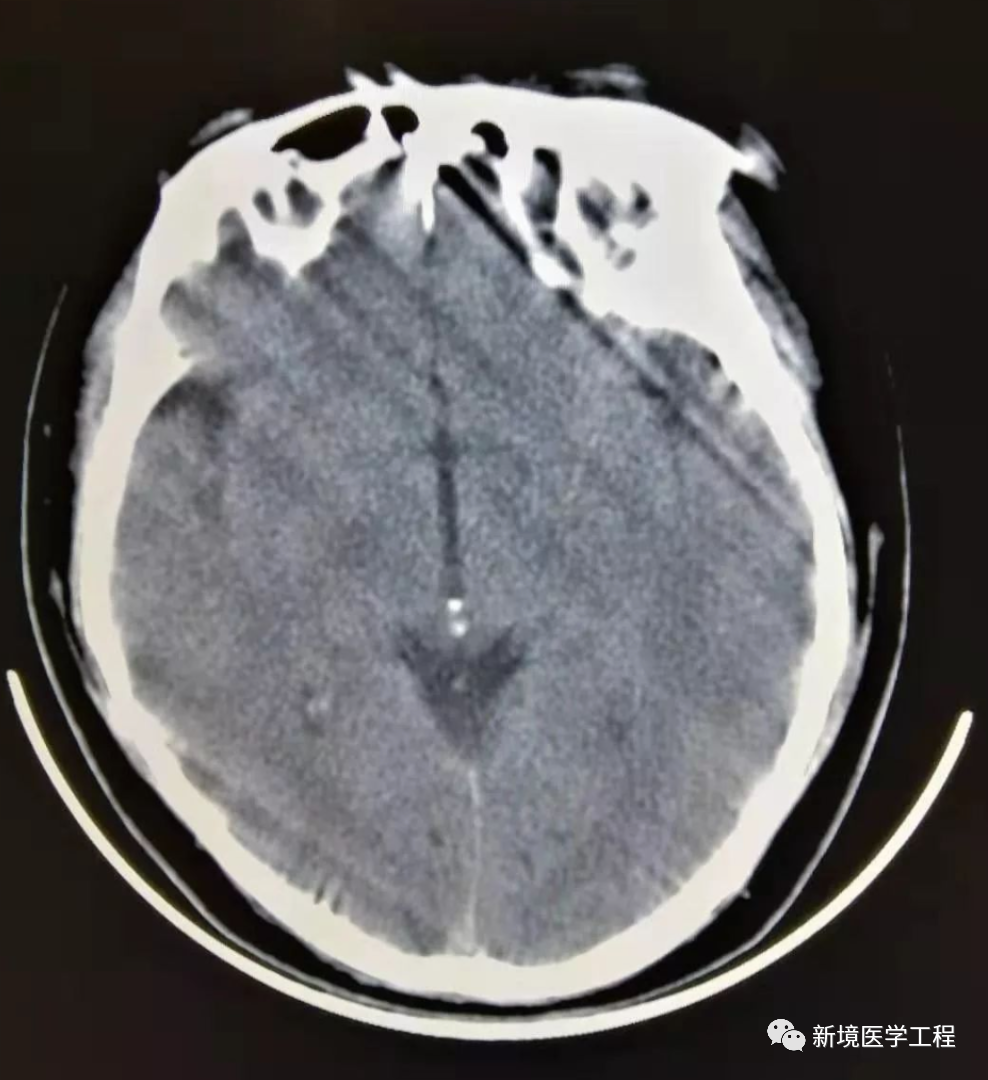

各种成像模式的原理和伪像发生的机制

伪像常见的表现机制;